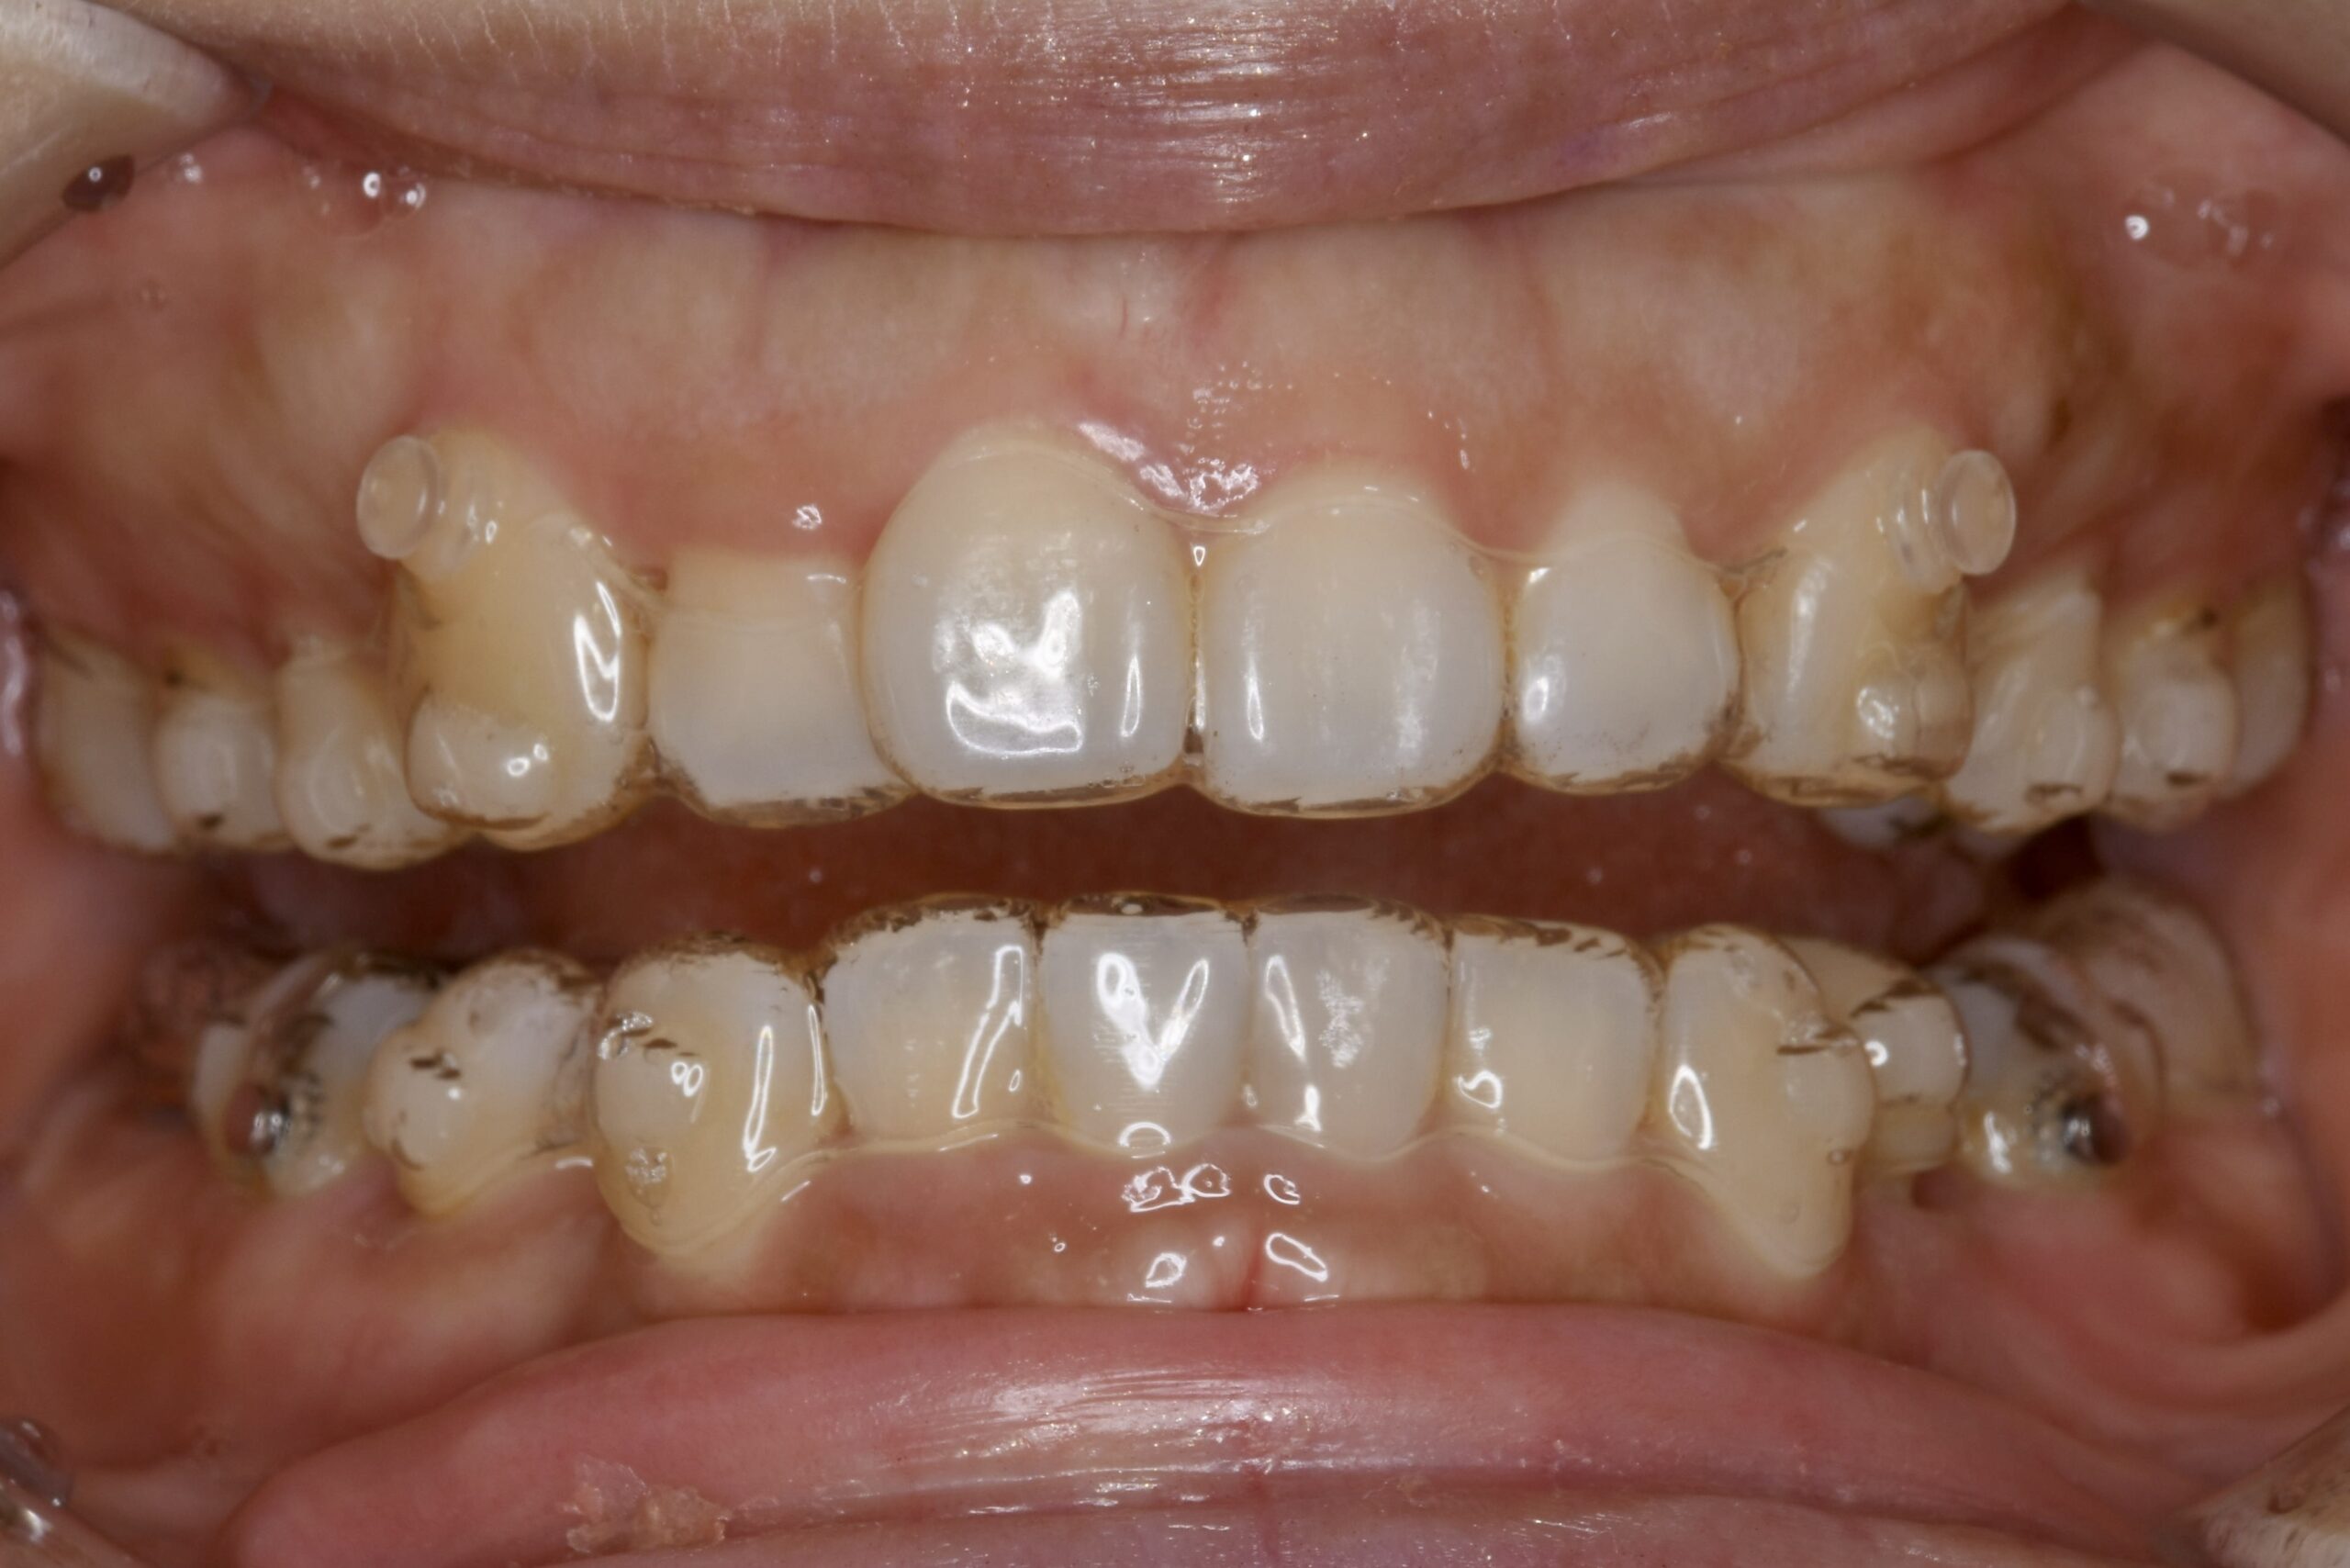

BEFORE

主訴 口元が出ていて気になる。

診断名・主な症状 叢生を伴う上顎前突

治療内容 上下とも歯を2本抜いて、上の前歯を後方に引きながら、でこぼこを治しました。

使用装置 マウスピース矯正装置(インビザライン)